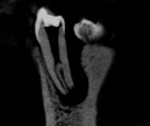

A 14-year-old female patient was referred to the endodontic specialization clinic of the Dentistry College of Recife in Brazil for endodontic treatment of tooth No. 21. During the anamnesis, the patient reported having had a history of painful symptoms in this tooth. Clinical examination revealed negative responses to thermal testing in cold mode (Endo-Ice, Coltene, coltene.com), percussion, palpation, and mobility testing. Upon periapical radiographic examination, the presence of a radiolucent image, suggestive of a periapical lesion, was verified, and an atypical anatomy was associated with the tooth in question (Figure 1). A CBCT was then taken in order to obtain a more in-depth and accurate diagnosis; it demonstrated the presence of a C-shaped canal (Figure 2 through Figure 4). The resulting diagnosis showed asymptomatic apical periodontitis. The endodontic treatment would be performed in two sessions.